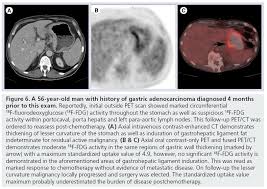

What Cancers Are Detected By Pet Scan / Mri Vs Pet Scan Which One You Should Get And Why : Any exposure to radiation carries a very small risk of potential tissue damage that could cause cancer at a later date.. These diseases include cancers, heart disease, endocrine, gastrointestinal or neurological. With that being said, not all cancers can be detected by pet. A pet scan is most often used when other tests, such as mri scan or ct scan, do not provide enough information or physicians are looking for the potential spread of the breast cancer to lymph nodes or beyond. It also can let you and your doctors know if cancer treatment is working. Pet scans use radioactively tagged molecules (or tracers) to image a wide array of molecular processes and when detected by a pet scanner, the tracers help your doctor to see how well your organs and tissues are working.

Pet Ct And Pet Mri In Ophthalmic Oncology Review from www.spandidos-publications.com Understanding the nature of cancer. Pet scans also prevent unnecessary surgeries and help suggest which cancer therapies are likely to be most effective for specific tumor types. Because of this high level of chemical activity, cancer cells the combined use of pet scans and ct scans is an effective method for detecting pelvic recurrences of rectal cancer. Pet scans use radioactively tagged molecules (or tracers) to image a wide array of molecular processes and when detected by a pet scanner, the tracers help your doctor to see how well your organs and tissues are working. A pet scan is particularly useful in detecting cancer because most cancers use more glucose than normal tissue uses. In this case, your body position will be very important. Cancer patients and their doctors now have access to a superior imaging technology in pet scans. A pet scan is most often used when other tests, such as mri scan or ct scan, do not provide enough information or physicians are looking for the potential spread of the breast cancer to lymph nodes or beyond.

A pet scan is not specific for cancer. It also can let you and your doctors know if cancer treatment is working. The scanner detects diseased cells that absorb. With that being said, not all cancers can be detected by pet. A pet scan, which uses a small amount of radioactive material, can help show if an enlarged lymph node is cancerous and detect cancer cells throughout the body that may not be seen on a ct scan. Positron emission tomography (pet) imaging scans use a radioactive tracer to check for signs of cancer, heart disease and brain disorders. The pet scan detects the concentrated psma tracer, pinpointing these tumors for more effective treatment. Psma pet imaging is a fda approved scan with more precise detection of prostate cancer for better treatment planning and targeted care. Most pet scans use a type of radiolabeled sugar to detect the cancer, as the majority of cancers grow quickly and need sugar for that growth. Pet can detect extremely small cancerous tumors, subtle changes of the brain and heart, and give doctors important early although cancer spreads silently in the body, pet can inspect all organs of the body for cancer in a single examination. Pet scans, short for positron emission tomography, can detect areas of cancer by obtaining images of the body's cells as they work. Ultrasound is also used to image the abdominal organs and kidneys. To determine whether the cancer has spread.

Those are detected by pet scanner and a computer converts a signal into detailed images showing how organs are working. Pet is speeding the detection of new drug weapons in the war on cancer. The tracer will collect in areas of. Positron emission tomography (pet) imaging or pet scan is a nuclear medicine imaging. Pet scans use radioactively tagged molecules (or tracers) to image a wide array of molecular processes and when detected by a pet scanner, the tracers help your doctor to see how well your organs and tissues are working. Pet scans are a type of test that create 3 dimensional (3d) pictures of the inside of your body. Pet scan is a special type of imaging test in which tracers are injected & are absorbed into organs of body and images are obtained. For cancer and disease detection, the most commonly used nuclear scan is an fdg pet scan. The pet scanner detects signals that are given off from the tracer. Pet/ct, which is a combination of positron emission tomography (pet) with computerized tomography (ct), is a powerful, essential tool for cancer detection and diagnosis. Diagnosis, cancer staging, treatment diagnosed with cancer and are undergoing active treatment, assess treatment response efficiency and perform cancer monitoring with pet/ct scan! A pet scan is not specific for cancer. With that being said, not all cancers can be detected by pet.